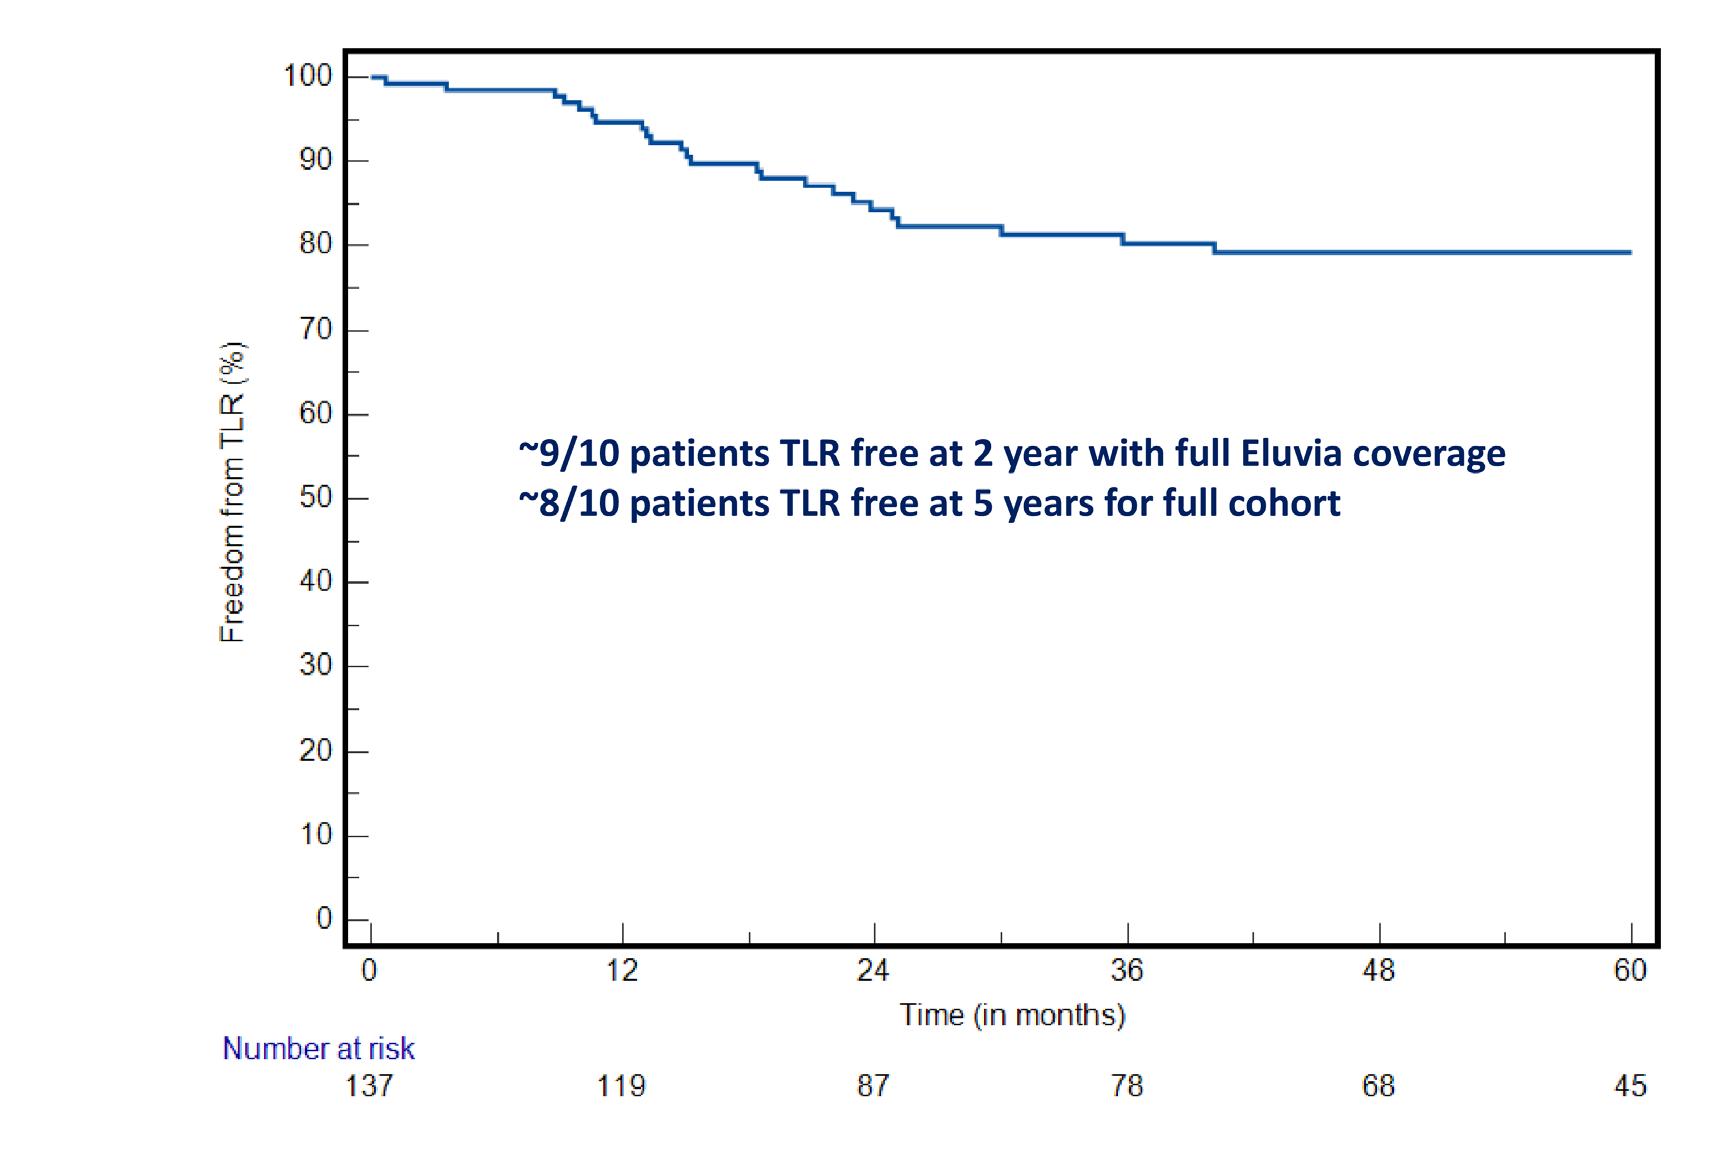

The Aperto® over-the-wire (OTW) DCB from Cardionovum—which is available in lengths of 20, 40 and 60mm and diameters from 4 up to 12mm—was developed specifically to solve unmet clinical needs in the treatment of haemodialysis access stenosis and recanalisation of arteriovenous fistula shunt grafts.

Tozzi, who is a full professor of vascular surgery at the University of Insubria, started using the Aperto in his vascular access practice over 10 years ago and is planning to soon publish his clinical experience in a study called Aperto 600.

Today, Tozzi explained, there is a pressing need for a device such as the Aperto. Haemodialysis patients now survive far longer than they used to, and therefore the key goal at present is to maintain patency of the access circuit to ensure that it can be used for several procedures over a long period of time.

“This goal has been achieved,” Tozzi reported, attributing this result to the Aperto. In his clinical practice, Tozzi shared that patients have a patent vascular access circuit without restenosis at one year after DCB treatment in the vast majority of cases.

Previously, Tozzi said, by way of comparison,

treatment being extended, with the average time in his centre now being eight months and only 6% of patients undergoing two or more procedures over the course of a year. “This is important for the patients, because it means less time in hospital,”

Tozzi commented.

treatment was limited to percutaneous transluminal angioplasty (PTA) alone, which at his centre resulted in no patients having a patent vascular access circuit at one year. The results with DCB, however, are “incredible”.

Tozzi was keen to stress that DCB is not the “final cure” for intimal hyperplasia. However, he underlined the importance of focusing on what the treatment option does offer in this regard. Significantly, he said, Aperto results in the mean time from first to second

While the efficacy of DCBs has been proven to be superior to that of PTA for these patients, there are limited data on their economic benefit. To rectify this, Tozzi noted that he has started a collaboration that aims to assess the cost benefit of DCBs in the vascular access failure population using the data coming from his Aperto 600 study combined with data from a metaanalysis of the available literature. The study looked at PTA alone compared to PTA with DCB.

He described the preliminary results from this economic analysis as positive, citing less time in hospital and less money spent on procedures, leaving more space in hospital to treat new patients and providing an opportunity to reduce waiting lists. “It is important to have the correct allocation of money and resources, so that we can treat more patients with less money,” he remarked.

Finally, Tozzi looked ahead to future guidelines regarding vascular access in haemodialysis patients. He highlighted the fact that the evidence base for DCBs continues to grow, and that the scientific community is waiting for this treatment option to be added to existing recommendations.

Tozzi concluded that, in his opinion, DCBs should now be viewed as a “first-line” treatment for stenosis and vascular access failure in haemodialysis patients.